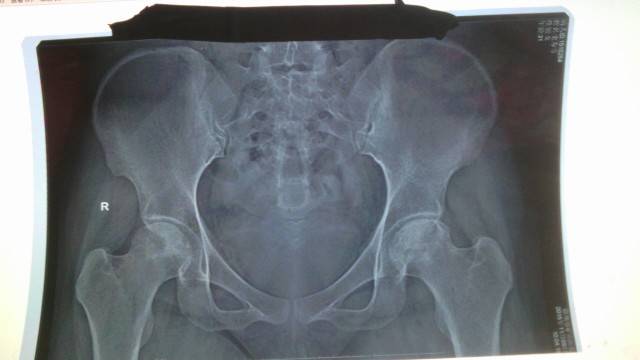

看片子没大有区别,不继续发展就是好的,不过,我是第二年就不太疼了,也是吃了中药,泡脚,加上TDP灯理疗等这些,现在不走时间长是不会疼,出门骑车买个菜,做个公交还可以